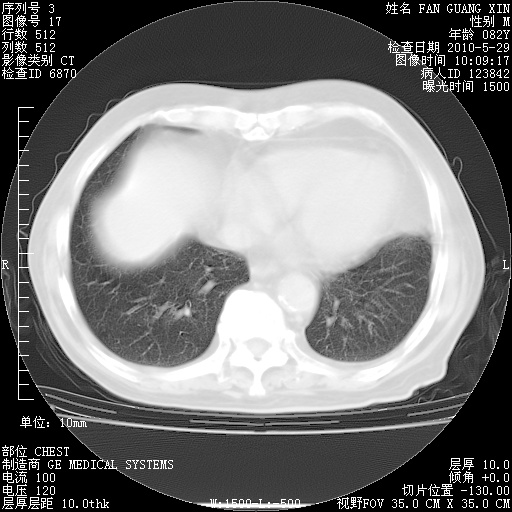

再治疗10天后的肺部CT

从白细胞总数和中性比例看好像合并感染。肺部纹理好像比上次多,支气管炎?其他感染?

阅读此次胸部CT,肺间质渗出性改变较入院时有吸收。目前从体温、白细胞、中性分叶明显增高,肯定存在细菌感染(发生医院感染哦,若无消化道及泌尿系统等感染的依据,肺部感染可能大)。若你院头孢哌酮舒巴坦钠耐药率较高,同意你的方案,若48小时体温仍高,可考虑使用碳青霉稀类抗菌药物,同时可予超声雾化、注意滴数时加大液体量。白蛋白33.30g/L较低哦,需加强营养等支持治疗。